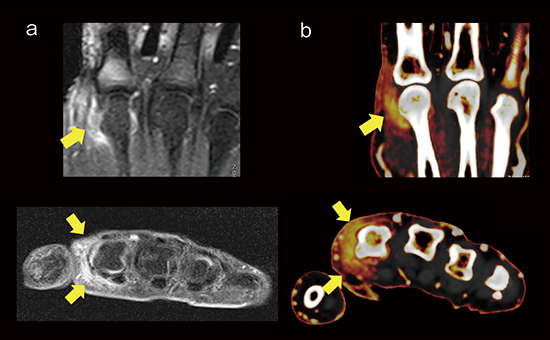

症例2は,64歳,女性,乾癬歴は11年。2010年から生物学的製剤としてインフリキシマブを投与していたが二次無効となり,アダリムマブに切り替えた。関節痛があり,DECTでは関節包を主体とした造影効果が認められるが,橈側側副靭帯に沿った炎症であり,滑膜炎は二次的と考えられた(図5 b)。MRIの脂肪抑制造影T1強調画像(図5 a)と比べても,DECTは炎症が明瞭に描出され診断が可能になっている。さらに,DECTでは,生物学的製剤を切り替えてから炎症が改善していることが一目瞭然にわかる(図6)。

図5 症例2:PsA(64歳,女性,乾癬歴11年)

a:MRI 脂肪抑制造影T1強調画像

b:DECTのヨードマップ画像